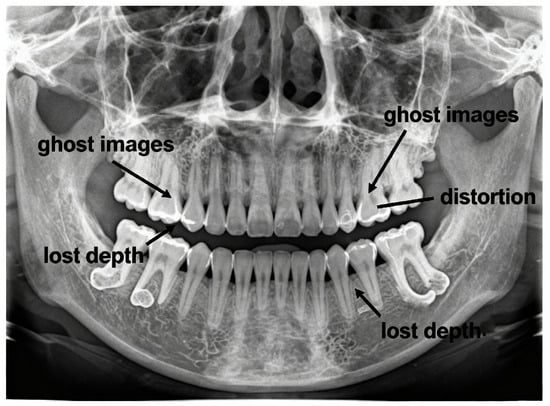

Recent advances in artificial intelligence and deep learning, particularly neural network architectures employing implicit representations and generative models, have demonstrated remarkable capability in reconstructing three-dimensional structures from limited two-dimensional projections [8,9]. These computational approaches offer the possibility of extracting 3D anatomical information from conventional panoramic radiographs—a challenging inverse problem that could bridge the dimensional divide between accessible 2D imaging and clinically necessary 3D visualisation. Figure 1 illustrates typical diagnostic challenges in panoramic imaging, including structural superimposition, ghost artefacts, magnification distortion, and loss of depth information.

Figure 1. Diagnostic limitations of panoramic radiography: ghost artefacts, geometric distortion, and loss of depth information.

Common artefacts further complicate image interpretation. Dense structures outside the focal trough can produce ghost images, while incorrect head positioning causes distortions such as tooth widening or the “smile/frown” curvature of the occlusal plane. Patient movement introduces motion blur, and limited spatial resolution (two to five line pairs per millimetre) restricts fine detail visibility. Superimposition of soft tissues and air spaces over dental anatomy adds further ambiguity, as panoramic imaging lacks the volumetric separation capability of CBCT [14].